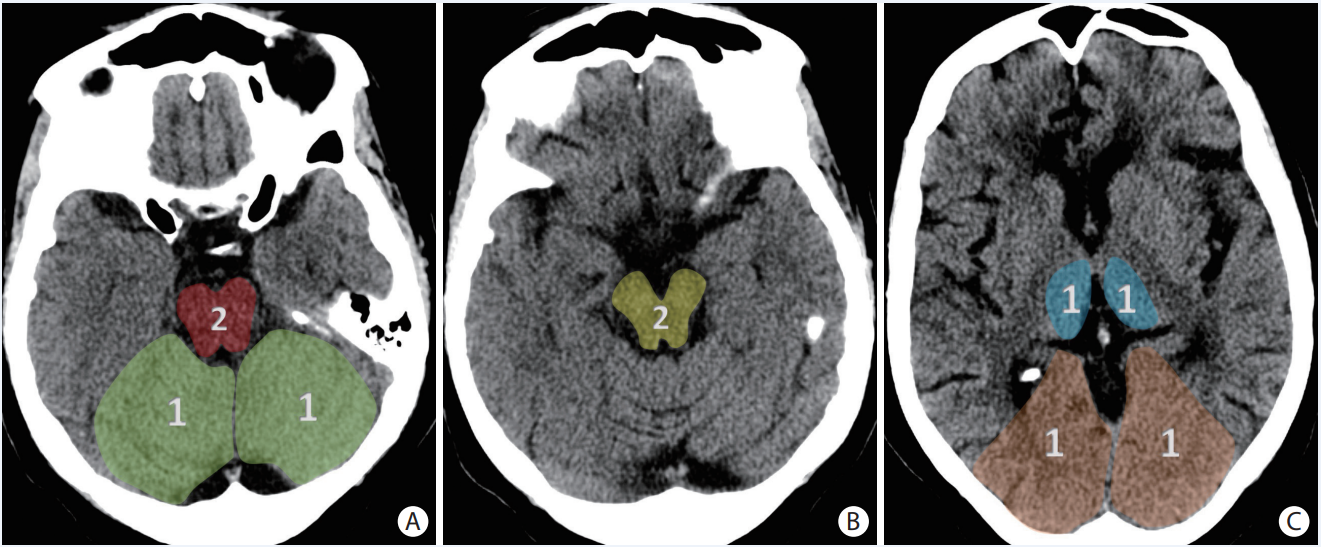

Explique o PC-ASPECTS

A

Total de 10 pontos, avalia circulação posterior

* Tálamos bilaterais (2 pontos: um para cada lado).

* Mesencéfalo (2 pontos).

* Ponte (2 pontos).

* Cerebelo (2 pontos: 2 pontos por hemisfério cerebelar).

* Lobo occipital (2 pontos: 1 ponto para cada lobo)